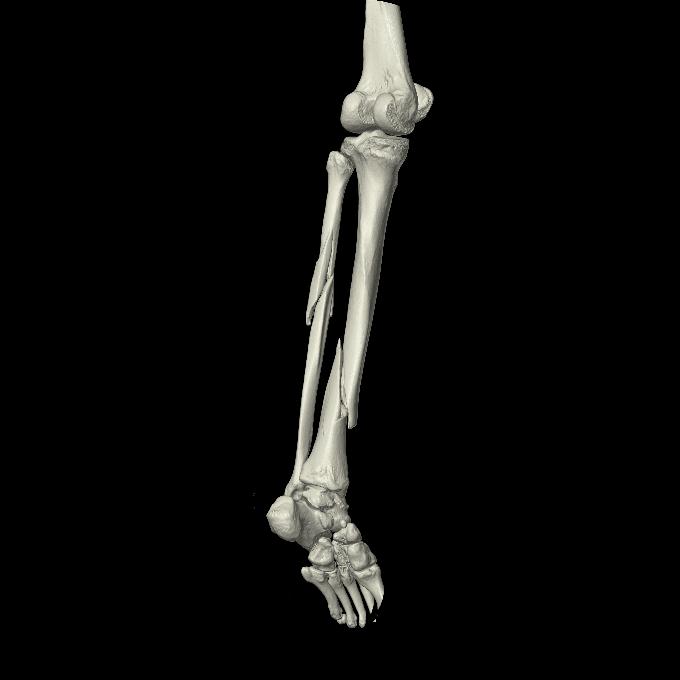

102803 1/12(キウスなし) 1/27 左下腿 4R 30歳女性 左脛骨軸内釘